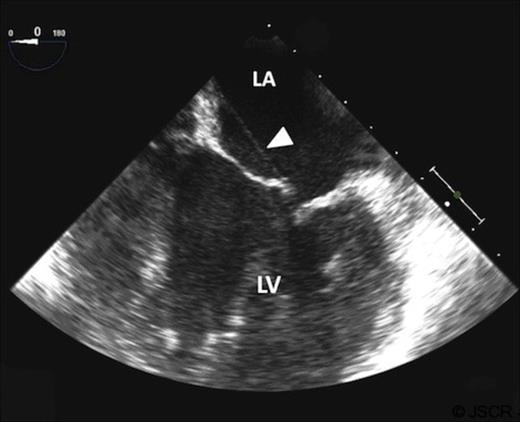

A 49 year old otherwise healthy black female presented with shortness of breath on exertion, paroxysmal nocturnal dyspnoea and orthopnoea. Her physical examination revealed a grade 4/6 pan-systolic murmur in the mitral area. Trans-thoracic and trans-esophageal echocardiogram revealed severe mitral regurgitation due to prolapse of the anterior mitral valve leaflet (AMVL), and a posteriorly directed regurgitant jet into the severely dilated left atrium was noted. An abnormal linear band was seen in the left atrium, connecting the A2 segment of the AMVL to the atrial septum and pulling the AMVL towards the left atrium (Figure 1). The left ventricle was hyperdynamic and moderately dilated. Estimated right ventricular systolic pressure was elevated to 50 mmHg, but the right ventricular function preserved. Therefore she was considered for mitral valve surgery.

Transoesopahgeal echocardiogram showing aberrant chord in the left atrium, extending from the anterior mitral valve leaflet to the left atrial septum (white arrow).